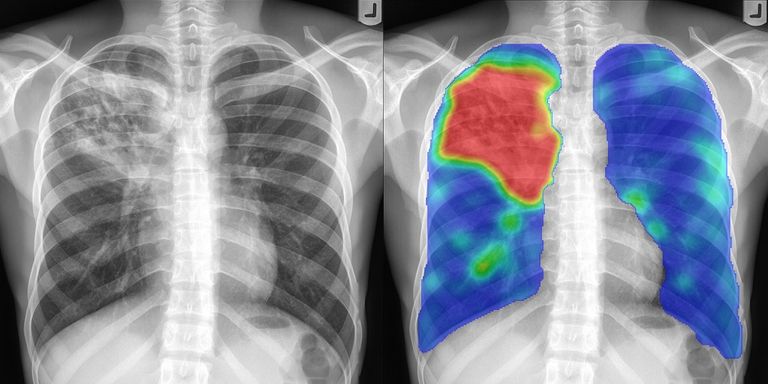

ANATOMY5Lessons · 2 hr

Internal organs

Musculoskeletal system

Anatomical features

X-RAY IMAGE ANALYSIS4Lessons · 2 hr 15 min

Principles of X-ray Image Analysis

Image Analysis

Examples with Real Prohibited Objects